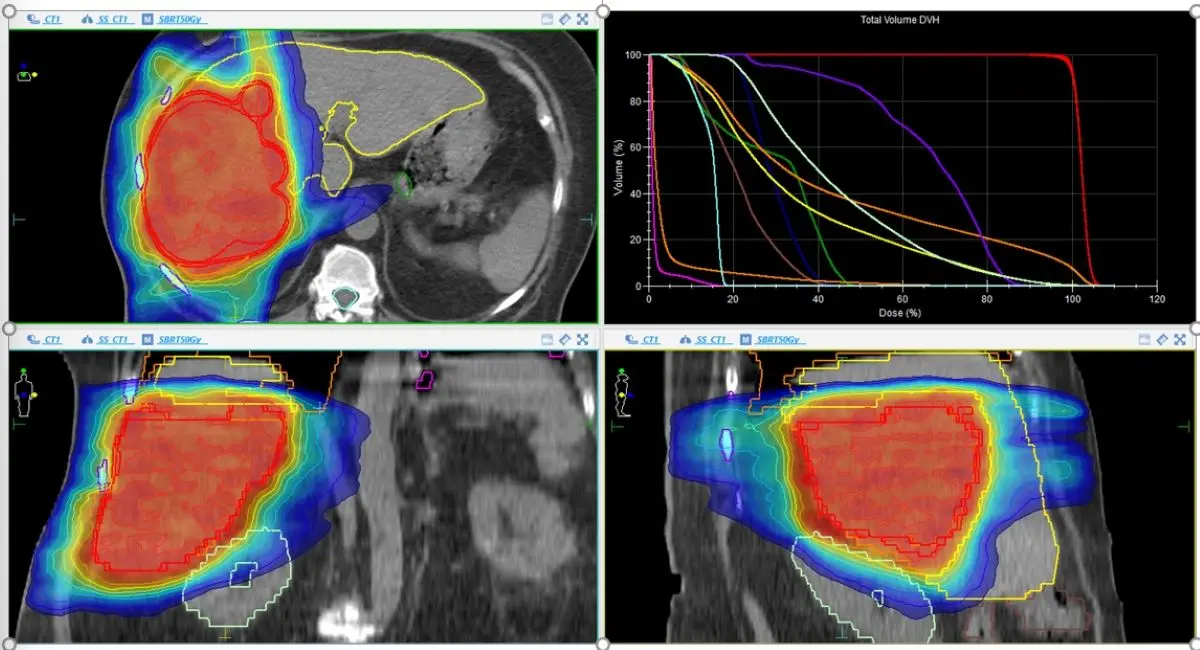

常佑康表示,SBRT是近年發展成熟的高精度放射治療,利用少次數、高劑量照射(每次約8~10Gy、總劑量達40~50Gy),可殺死腫瘤細胞並保留周邊肝臟功能;不同於傳統治療需連續接受20~30次小劑量放射線,SBRT大幅縮短療程、提高治療效率,對於無法手術的患者是一項關鍵選擇。

此外,常佑康說,為確保照射準確性,進行SBRT之前會以儀器壓迫橫膈膜以控制腫瘤移動,再透過3組電腦斷層掃描分析腫瘤隨呼吸變化的軌跡,計算後的治療還會搭配即時影像引導,以3D定位系統精準對準腫瘤,將傷及正常消化器官的風險降到最低。